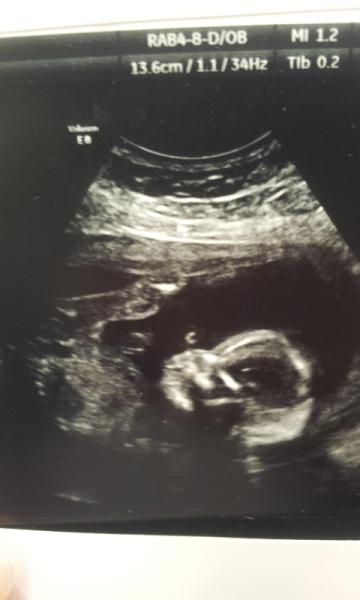

ldt87 · 12/05/2014 20:18

Here's mine, not as clear as yours kirsti! It's fab, congrats on having a good scan and getting a good look around xx